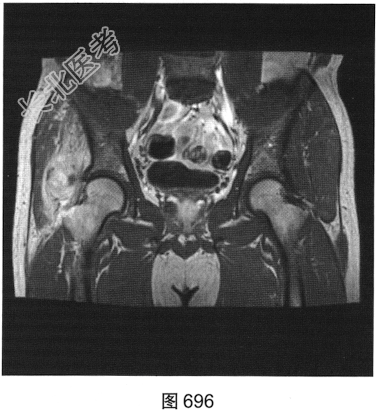

- 多项选择题2.[提示]患者行MRI平扫及增强扫描,见图692~图697。患者MRI平扫及增强扫描图像有哪些阳性表现( )

A、肿块边界不清,信号不均匀

B、肿块周围水肿明显

C、增强扫描肿块呈均匀强化

D、肿块边界清楚,信号均匀

E、增强扫描肿块及周围软组织呈明显不均匀强化

F、与邻近肌肉相比,T1WI呈等信号;T2压脂序列呈明显高信号